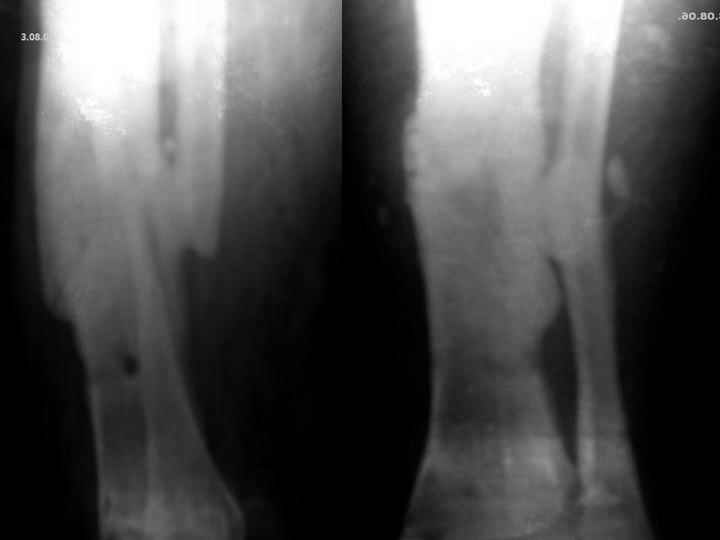

Мужчина, 29 лет. Состоит на лечении в ЦРБ.Диагноз: Замедленно сростающийся со смещением повторный перелом обеих костей левой голени вс/3-н/3, состояние после ВЧКО, хронический остеомиелит костей левой голени, свищевая форма,трофический синдром, смешанная контрактура левого коленного, голеностопного суставов.

Травма 20.12.04. - открытый 2Б тип, оскольчатый перелом обеих костей левой голени в с/3-н/3 сосмещением отломков (ДТП). 20.12.04.- ВЧКО костей голени АВФ спице-стержневого типа, ПХО ран.Лечился амбулаторно. Перелом длительно не сростался. АВФ демонтирован 22.06.05., разрешена нагрузка на ногу, после чего появилась подвижность в области перелома. 8.07.05. - ВЧКО, туннелизация по Беку. Течение осложнилось развитием спицевого остеомиелита, 1.11.05. АВФ демонтирован, получал консервативное лечение. После нормализации состояния 17.11.05.- секвестрэктомия, ВЧКО голени.12.04.06. АВФ демонтирован.

3.06.06.повторная травма - закрытый повторный перелом левой б/б кости в с/-н/3, лечился методомгипсовой иммобилизации.

Место болезни - ось голени искривлена. Kеллоидные рубцы в местах проведения спиц, по передней поверхности голени. По передней и внутренне-боковой поверхности голени в определяется 3 свища с умеренным серозным отделяемым. Отек голени и сустава, движения в коленном и голеностопном суставах ограничены, неврологических расстройств в стопе нет.

Снимки, конечно, оставляют желать. Ладно, пробуем предложить решение в условиях недостатка информации. В том числе не зная о доступных на месте методах лечения.